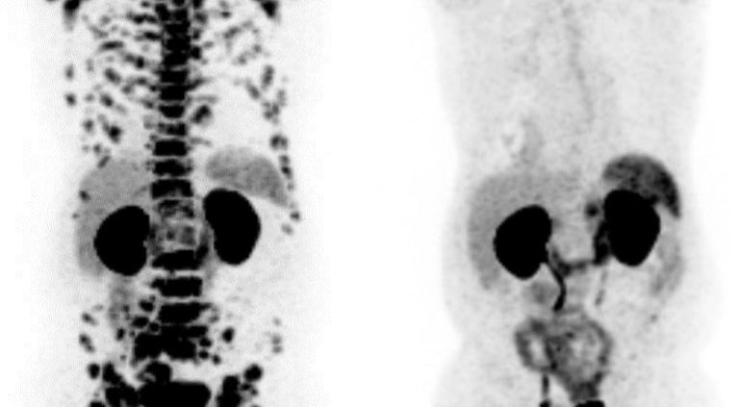

美國Serva Energy(Serva)公司開發(fā)了一種基于反應(yīng)堆的生產(chǎn)方法,以增加錒-225 (Ac-225)的供應(yīng)。該公司表示,錒-225是一種治療癌癥的放射性同位素,腫瘤學(xué)研究人員和開發(fā)靶向α療法(TATs)的制藥公司對它都有“超高的需求”,這是在抗擊癌癥方面邁出的有希望的一步。